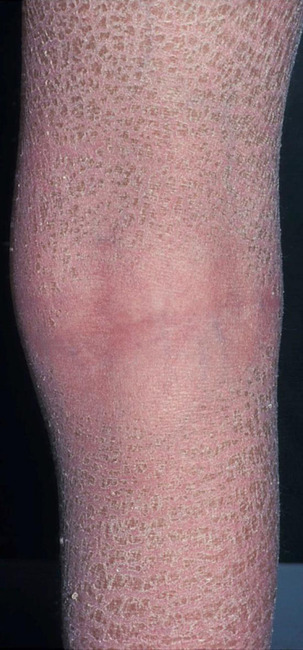

Genetic defects in lipid metabolism or in the protein components of the stratum corneum are also accompanied by skin barrier defects, such as in ichthyosis and related cornification disorders. Atopic dry skin has an impaired barrier function due to abnormalities in enzymes and lipids in the stratum corneum resulting in increased transepidermal water loss, lower water-binding capacity and vulnerability to Staphylococcus aureus colonisation. Examples are provided in Figures 11 and 12.

image

Figure 11 - Impaired skin barrier in a patient with ichthyosis